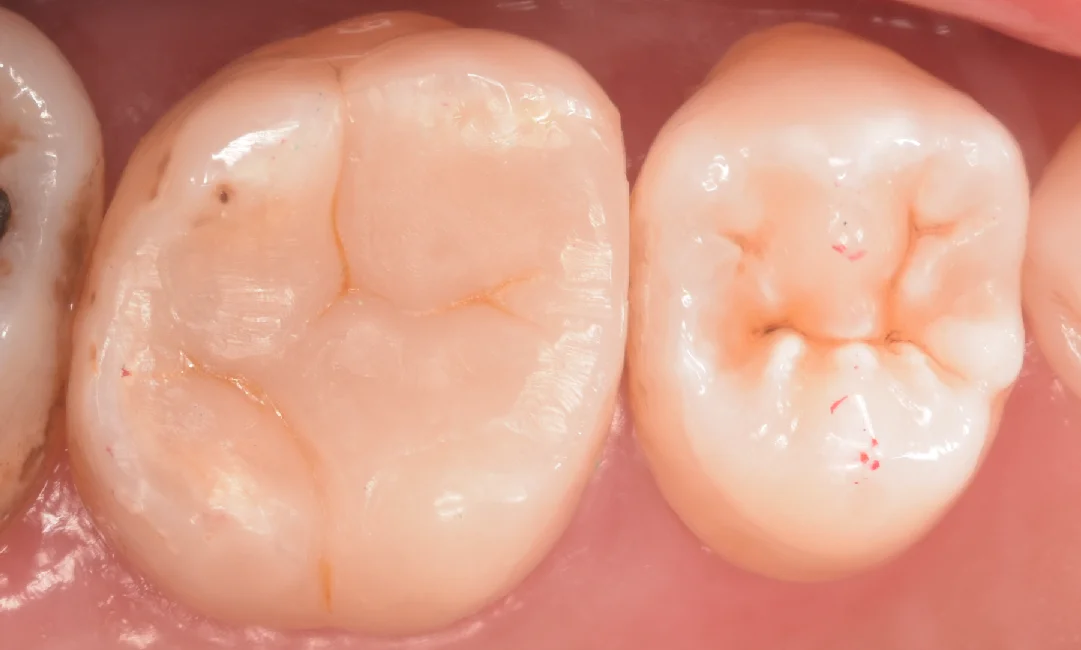

虫歯を取り切ったのがこちらになります。

神経が相当ギリギリでしたね・・・

また歯茎からはおおよそ1.5mmほど深くまで虫歯になっていました。

歯茎を傷つけずに除去できたため、1.5mm深くとも歯茎からの出血はありません。

また、今回は接着操作を確実に行うためにラバーダム防湿を行いました。その写真がこちらです。

歯茎の深い部分をしっかりと封鎖することで十分な乾燥が行えるため接着能力を最大限に発揮することができます。

また隣の歯に接着剤の材料が付いてしまうと綺麗に詰められないので保護するシールを貼って処理を行いました。

(このラバーダム防湿ですが、うちで使ってるラバーダムは単価が高いにも関わらず保険点数に入っていないため、保険診療では行なっておりませんので、その点はご注意ください。)

そして詰め終わったのがこちらになります。

ある程度違和感なくしっかりと詰められたかと思います。